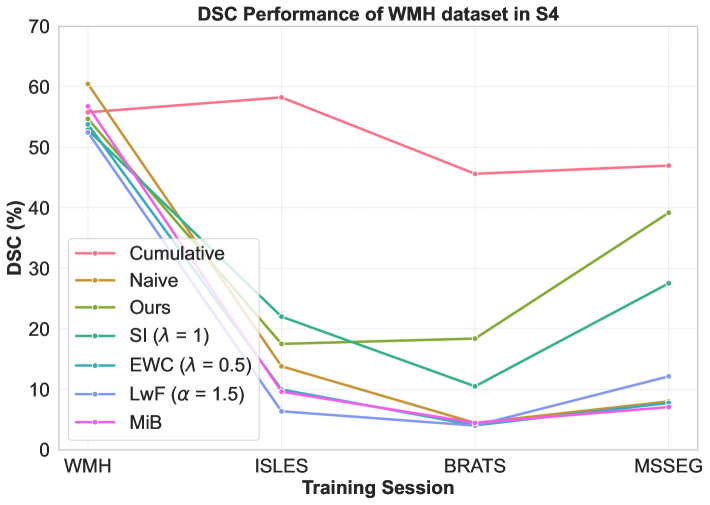

We compare the proposed strategy against popular CL strategies, including EWC [Kirkpatrick et al.(2017)Kirkpatrick, Pascanu, Rabinowitz, Veness, Desjardins, Rusu, Milan, Quan, Ramalho, Grabska-Barwinska, et al.], SI [Zenke et al.(2017)Zenke, Poole, and Ganguli], LwF [Li and Hoiem(2018)], MiB [Cermelli et al.(2020)Cermelli, Mancini, Bulo, Ricci, and Caputo], Replay [Rolnick et al.(2019)Rolnick, Ahuja, Schwarz, Lillicrap, and Wayne], and GDumb [Prabhu et al.(2020)Prabhu, Torr, and Dokania] in 3D-UNet. To establish baselines, we report lower bound performance with naive, and upper bounds with cumulative and joint training. Naive corresponds to traditional fine-tuning on new datasets, joint training uses all datasets simultaneously, and cumulative training sequentially incorporates all previous data. Experiments were conducted using Avalanche 0.6.0 framework [Lomonaco et al.(2021)Lomonaco, Pellegrini, Cossu, Carta, Graffieti, Hayes, Lange, Masana, Pomponi, van de Ven, Mundt, She, Cooper, Forest, Belouadah, Calderara, Parisi, Cuzzolin, Tolias, Scardapane, Antiga, Amhad, Popescu, Kanan, van de Weijer, Tuytelaars, Bacciu, and Maltoni]. The buffer size was set to for Replay and GDumb. Regularization factors ( in LwF and in SI and EWC) were tuned within 0.5, 1.0, 1.5, 2.0, and was fixed at . For our method, we set , , and . For domain-conditioned MoE, we consider maximum modalities as (PD, FLAIR, T1, T1c, T2, DWI) and pathology as (Tumor, Stroke lesion, Sclerosis lesions, White matter hyperintensity). An example of the binary domain-conditioned token () for a sample with FLAIR and T1 modality and “stroke lesion” pathology would be [0, 1, 1, 0, 0, 0, 0, 1, 0, 0]. We tested on four dataset sequences: S1 (high to low dataset size: {BRATS, ATLAS, MSSEG, ISLES, WMH}), S2 (descending modality count: {MSSEG, BRATS, ISLES, WMH, ATLAS}), S3 (low to high dataset size: {ISLES, WMH, MSSEG, BRATS, ATLAS}), and S4 (ascending modality count: {ATLAS, WMH, ISLES, BRATS, MSSEG}).

Performance comparison with others: For the considered medical applications, the primary concern will not be on improving zero-shot performance (FWT) but rather on minimizing forgetting (BWT) and enhancing the average DSC of the model (ACC and ILM). While FWT is reported for completeness, our analysis emphasize ACC, ILM, and BWT. Table 2 presents the ACC, ILM, BWT, and FWT values for all methods across sequences S1, S2, S3, and S4. Across all sequences, CL approaches (GDumb, Replay, MiB, LwF, SI, EWC, and the proposed method) mostly outperform naive training, highlighting the importance of mechanisms to mitigate catastrophic forgetting in UNet-based segmentation tasks. Further, as expected, approaches storing past data partially (Replay, GDumb) or fully (cumulative, joint training) show higher performance compared to methods (naive, MiB, LwF, SI, EWC, and the proposed approach) with no access to past exemplars. When comparing the proposed method to other buffer-free approaches (MiB, LwF, SI, EWC), it consistently achieves superior performance in all the sequences S1, S2, S3, and S4. Unlike these existing CL methods, which penalize large deviations from previously learned weights through response-level regularization terms in the training loss, the proposed approach introduces a drift-based dynamic penalization factor along with a latent-level regularization. This drift-based dual distillation allows for more effective mitigation of catastrophic forgetting. The proposed method shows a positive gain in (ACC, ILM, BWT) over best performance achieved among state-of-the art buffer-free approaches (blue colored in Table 2). Specifically, we observe an improvements of (25.51%, 9.23%, 34.34%) in S1, (6.57%, 25.28%, 31.85%) in S2, (4.85%, 11.02%, 40.15%) in S3, and (7.67%, 10.65%, 17.62%) in S4. For intuitive visualization, radar plots for S1, S2, S3, and S4, comparing cumulative, naive, the best-performing buffer-free methods, and the proposed approach are provided in Fig. 6 of Appendix.

Performance of a dataset in different sessions: We closely analyze CL model’s performances on first/second dataset upon learning other datasets in a given sequence. Specifically, Figure 3 shows DSC for BRATS in S1 and S2, ISLES in S3, and WMH in S4, with cumulative training included for reference. While cumulative training offers stable results, it requires access to all previous datasets, which is impractical in real-world scenarios. The naive approach shows significant DSC degradation, with high standard deviations of 33.91 (S1) and 40.23 (S2), 26.31 (S3), and 24.78 (S4) reflecting instability. In contrast, our CL strategy maintains stability, with much lower standard deviations of 5.19 (S1), 14.51 (S2), 11.37 (S3), and 15.50 (S4) highlighting its increased robustness against forgetting. Other buffer-free CL methods (MiB, SI, EWC, LwF) show better performance than naive training (Table 2) but still exhibit instability in DSC, with standard deviations of (28.80, 17.86, 31.14, 25.98) for S1, (36.75, 36.75, 35.85, 40.10) for S2, (25.43, 23.51, 25.65, 25.11) for S3, and (25.06, 15.51, 22.84, 23.55) for S4. While these methods perform well for natural images, their effectiveness is limited in brain MRI segmentation under domain shifts. In contrast, our approach delivers better stability and mitigates catastrophic forgetting effectively. Detailed segmentation visualizations for BRATS are provided in Appendix A.

Impact of dataset orders: We study the impact of different sequences on overall performance. We analyze ACC, ILM, BWT by best performing other CL methods and proposed approach for S1-S4 in Table 2 (summarized in Table 4, Appendix). We can see that best ACC is poor in S2 (28.54) and S3 (35.85) as compared to that in S1 (54.31) and S4 (50.67). Notably, all methods (except EWC) showed performance degradation when ATLAS (a single-modality dataset) was introduced later in sequences (S2, S3), adversely impacting the generalization of previously acquired knowledge in the model. This occurs because “modality dropping”, a critical generalization technique, cannot be applied to ATLAS due to its single-modality nature. Consequently, learning ATLAS in the later stages negatively impacts the model’s prior generalization capability. In contrast, when we learn datasets with fewer modalities at the start of sequences (S1 and S4), their negative effect is covered at later stages when we learn datasets with more modalities.